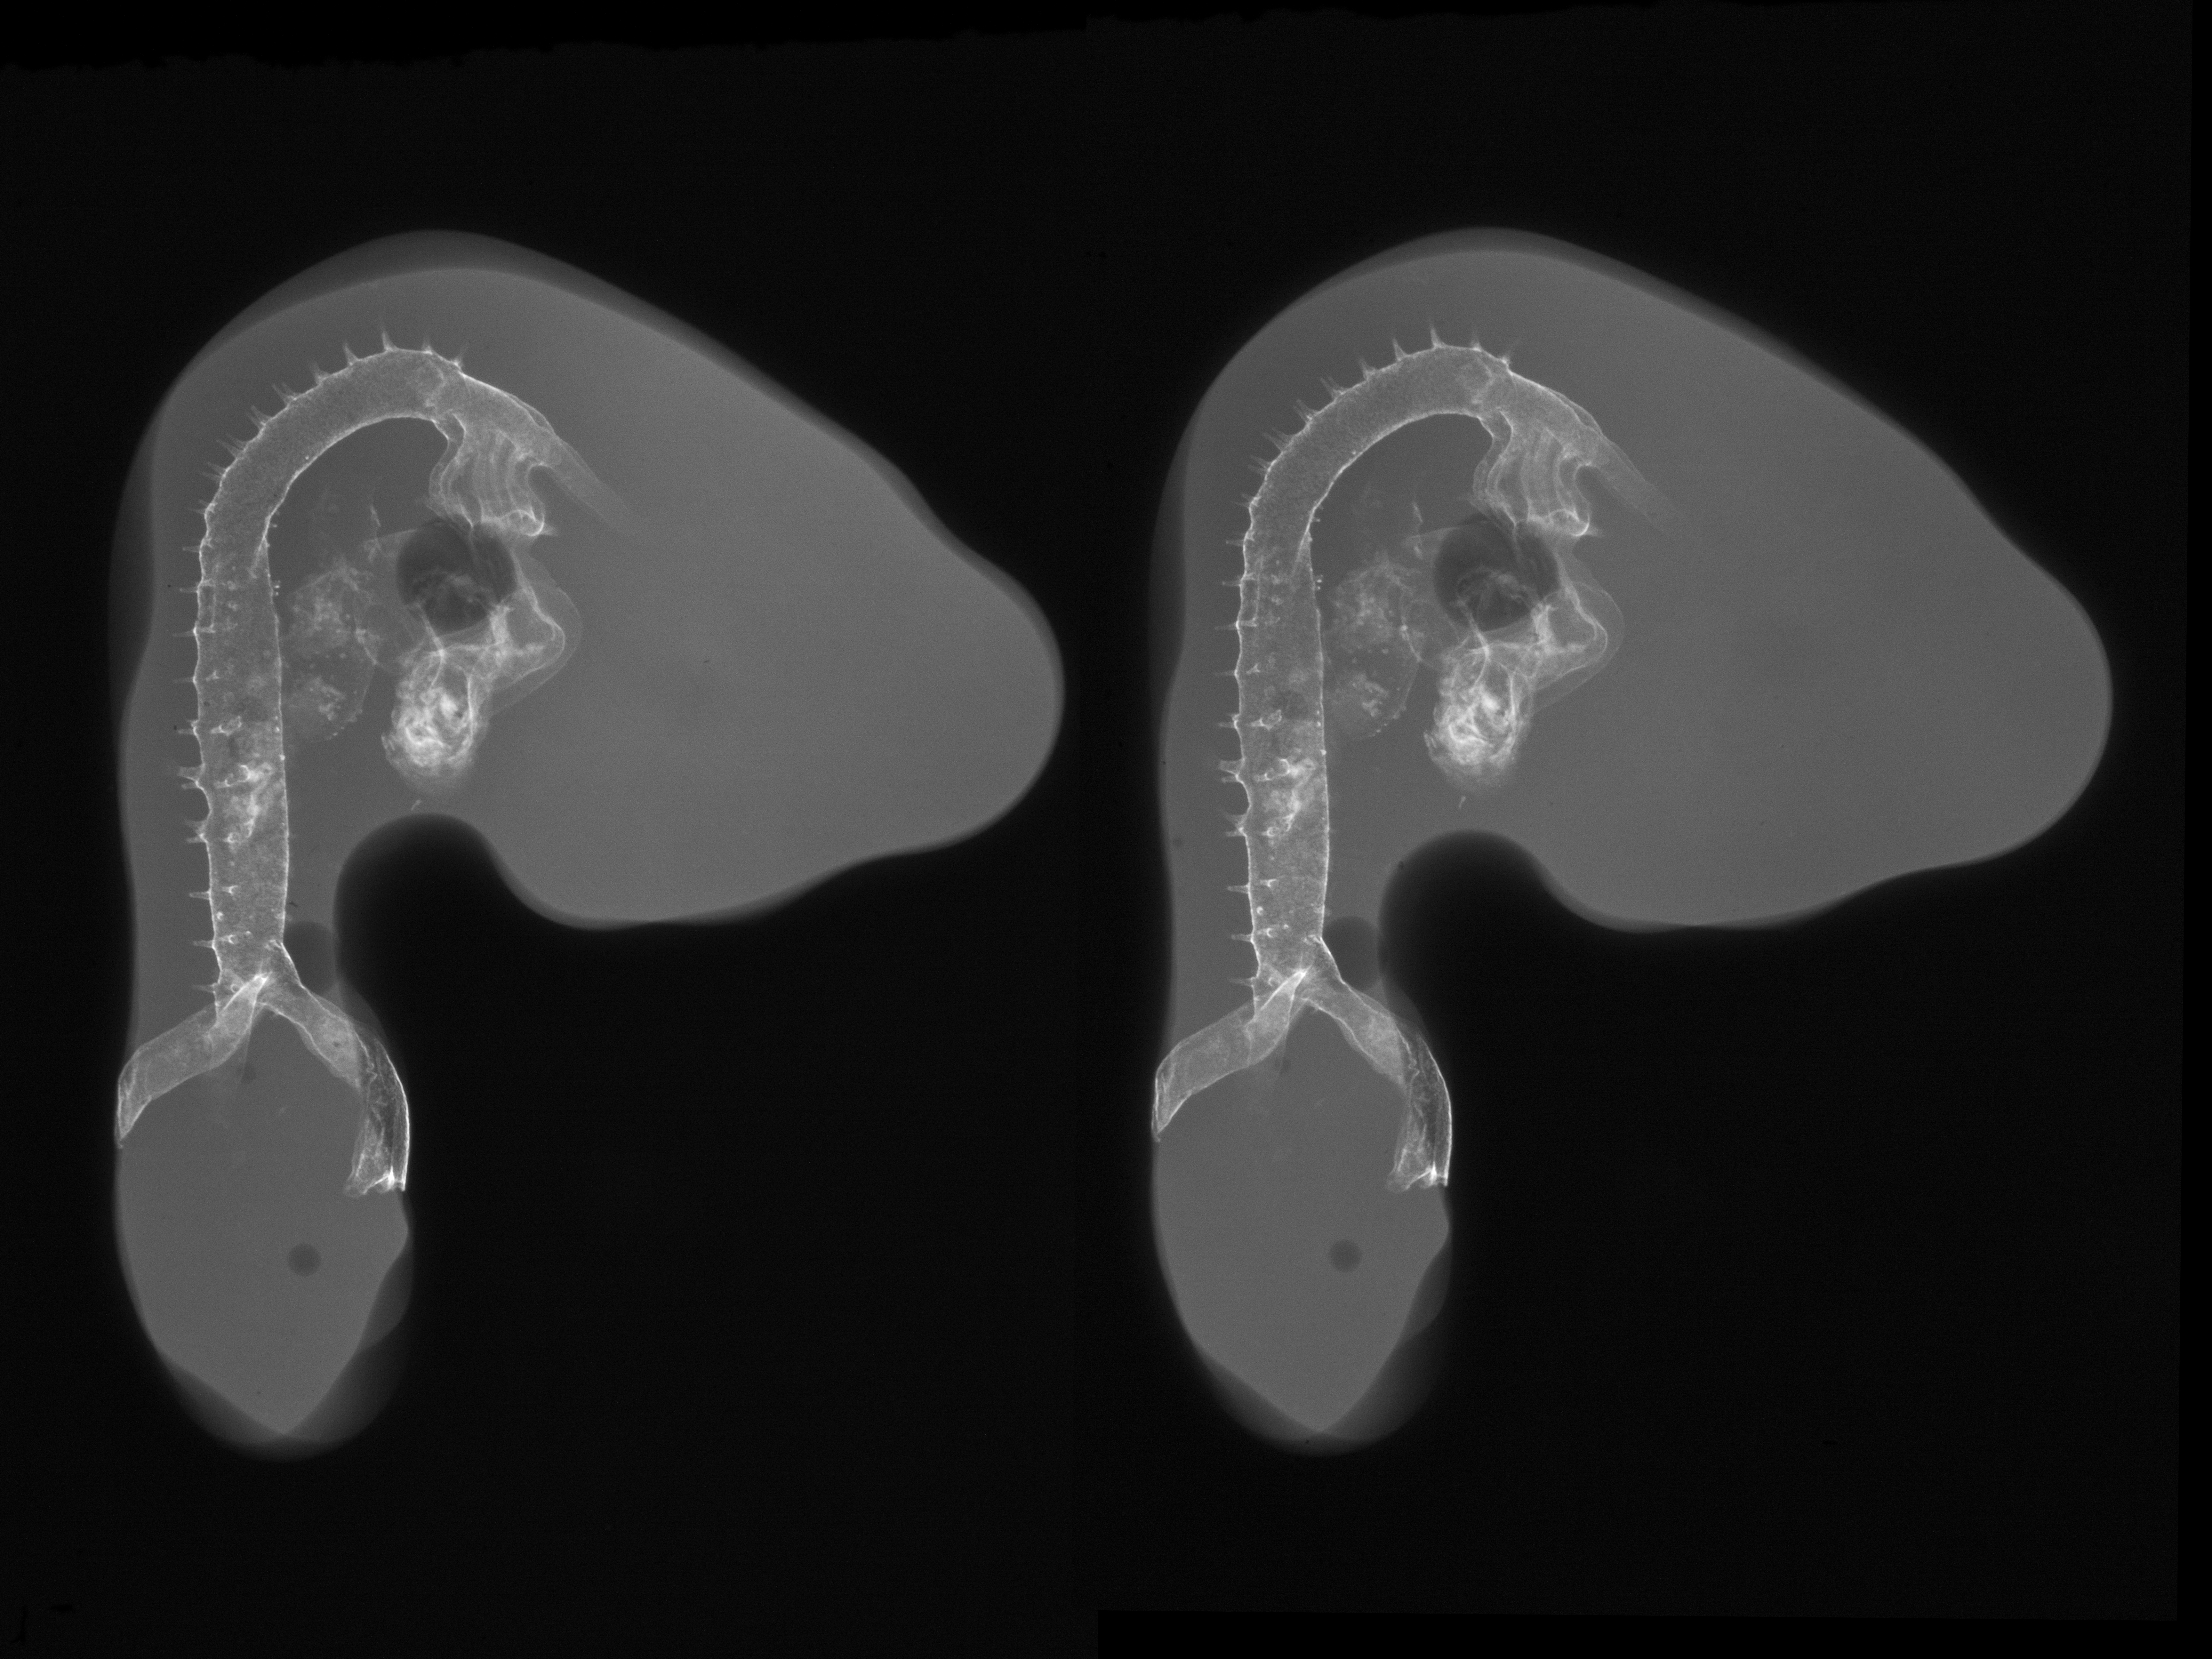

Chick Embryo Microangiography

Hamburger-Hamilton (HH) Stage 21 (approx. 3.5 days)

X-Ray Micrographs

Stereo X-Ray Micrographs